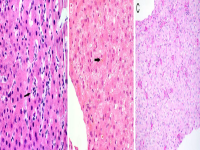

王功伟老师肾脏肿瘤系列讲座(二十九)一个好汉三个帮:嫌色细胞肾细胞癌病理诊断基础